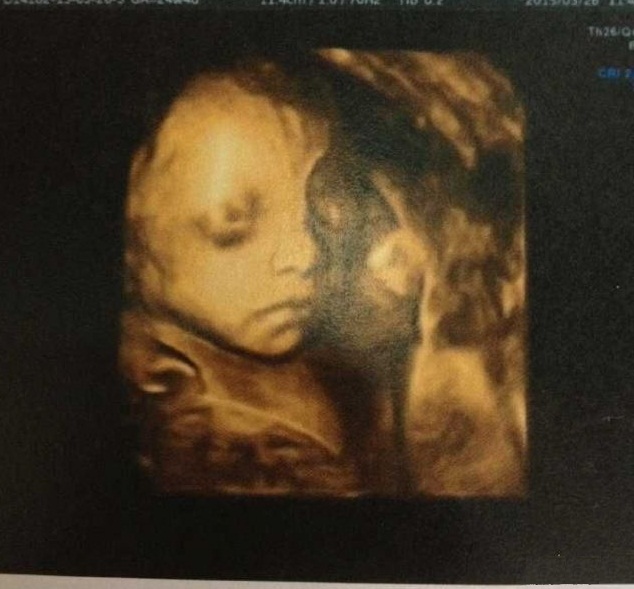

孕24周:孕期最令人激动的产检便是照四维啦,第一次看到宝宝的长相,真的是孕期最有趣的产检我在市妇幼照的四维照,遇到了非常棒的B超医生,她大概50多岁的样子,因为四维是大排畸检查难免会很紧张,她B超做得很认真偶尔会跟我说两句话,告诉我宝宝很活泼老是用手挡着脸不让她拍照。终于拍到了宝宝的照片,她笑着说毛毛长得蛮漂亮!